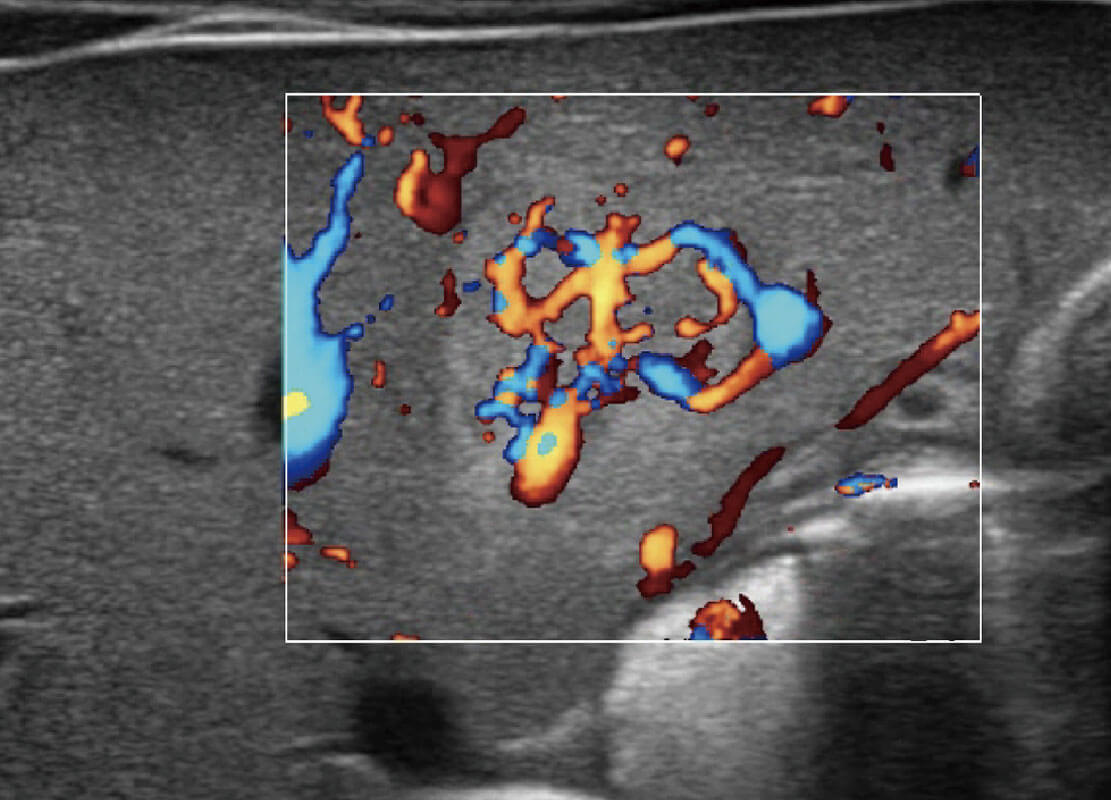

P60搭载宽频带线阵探头、宽景成像、弹性成像技术,为您提供乳腺应用方案。P60支持高频相控阵探头、线阵探头、腹部高频探头、腹部微凸探头等,丰富的探头群搭载敏感的彩色血流成像,适用于新生儿多种脏器检测要求,满足新生儿筛查需求。

乳腺癌显微血流

新生儿肝血管癌